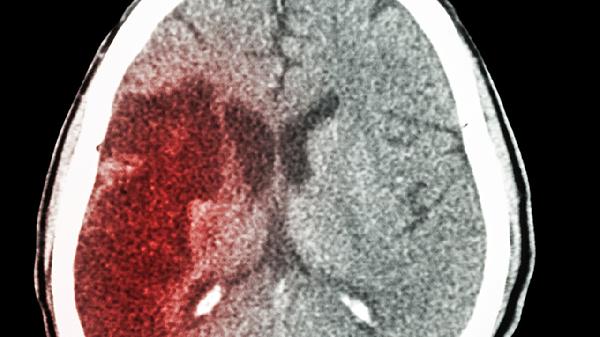

医生发现:能活过85岁的脑梗患者,大多在确诊之后,做了这3件事

脑梗后还能活到85岁?这听起来像天方夜谭,但确实有人做到了。仔细观察这些长寿的脑梗患者,会发现他们身上有着惊人的相似之处。不是靠运气,而是掌握了一套独特的生存智慧。